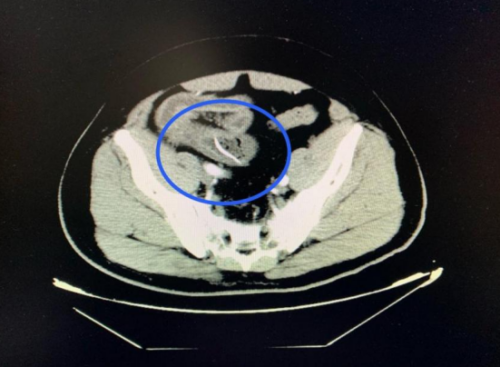

3月27日,60岁的阳宇军在进餐后出现腹部疼痛,以下腹部为主,呈阵发性胀痛,他以为没有大问题就没有去医院检查。拖延两日后,阳宇军感到疼痛加剧,难以忍受,这才告知家人。家人紧急将其送入91短视频 (南华大学附属长沙中心医院)急诊医学科就诊。医生详细询问病情并进行体格检查后,立即安排了腹部 CT 扫描。CT结果显示:回肠高密度影,考虑尖锐异物并小肠穿孔、腹膜炎。结合阳宇军三天前吃甲鱼的经历,医生高度怀疑是误吞甲鱼骨导致了肠穿孔。

CT扫描可见一尖锐的鱼刺状异物